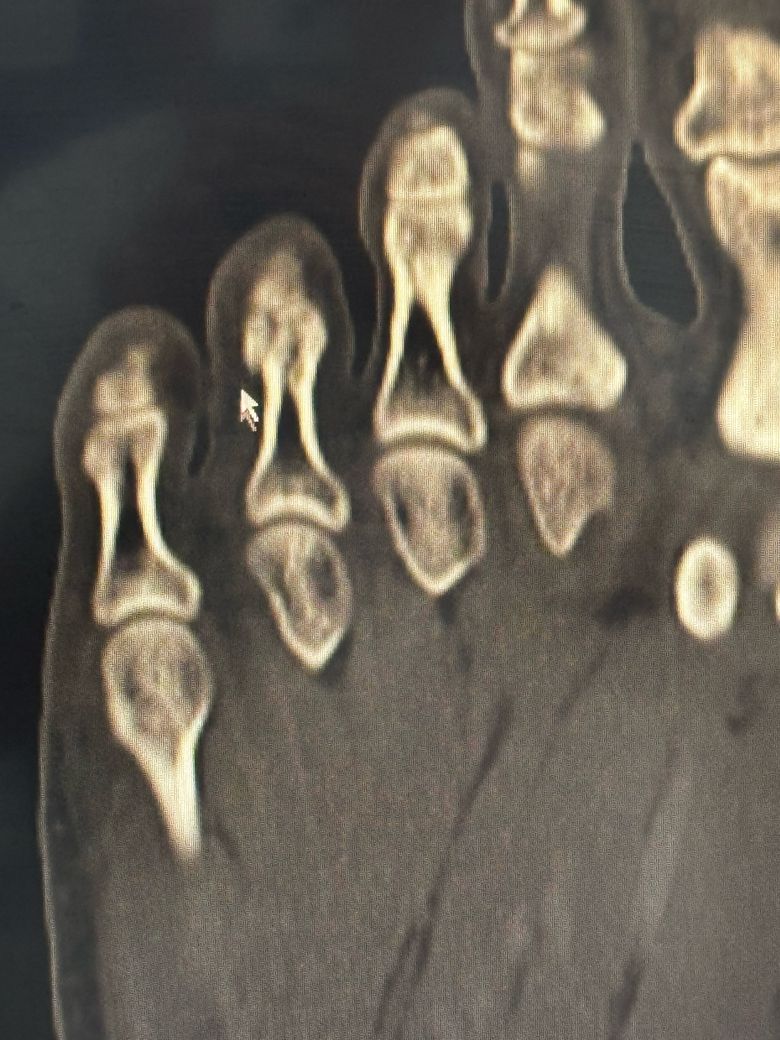

• 2번 째 사진

이미지상 발가라 뼈에 금이 가거나 골절 소견이 있어보이지만 정확한 수술 여부는 골절의 위치 각도 뼈 어긋남 여부에 따라 다릅니다.

발가락 골절로 인한 수술 관련해서 질문을 주셨는데 골절의 정도 및 어긋남 정도 그리고 증상에 따라 수술 여부가 결정될 수 있으며 발가락이 휘어져 보이거나 뼈가 많이 어긋나거나 관절에 영향을 주는 골절 같은 경우 수술이 필요할 수 있습니다.